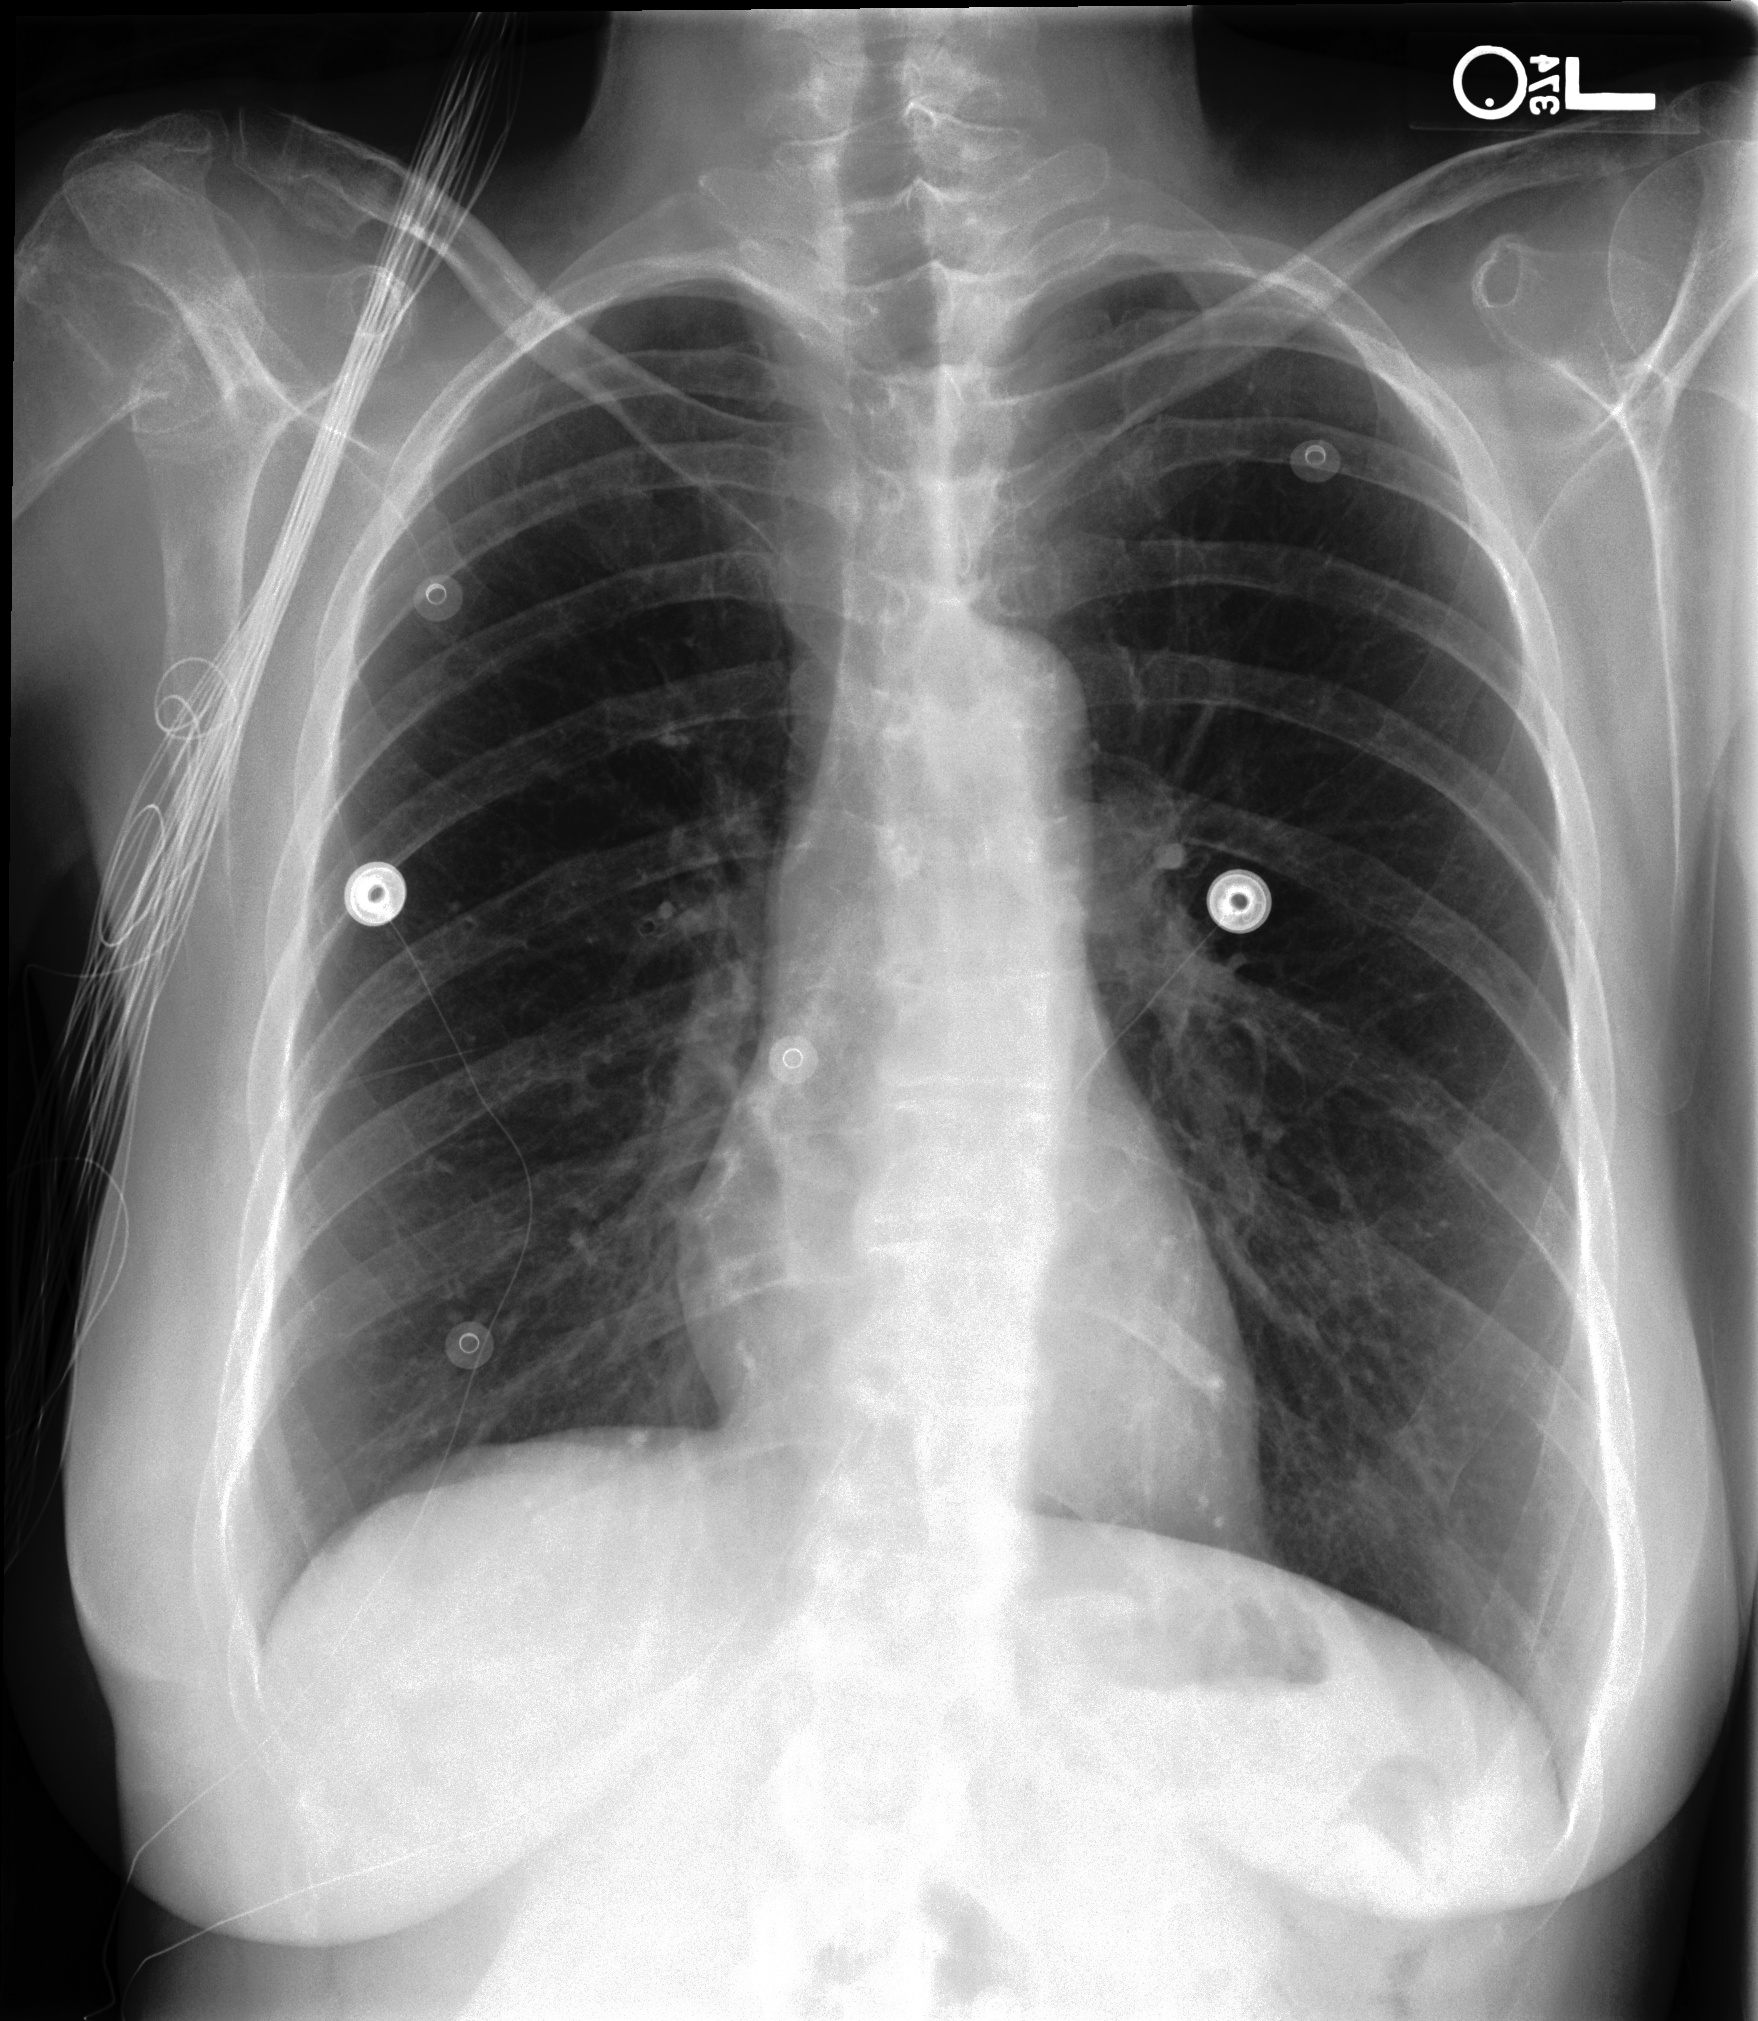

Chest X-Ray Ground Truth Our predictions

[Uncaptioned image] 1. Stable bilateral small pleural effusions and atelectasis. 2. Enlarged pulmonary artery, suggesting pulmonary hypertension. No significant interval change. Bilateral small pleural effusions and adjacent atelectasis are overall unchanged. The heart is top-normal in size, unchanged. The pulmonary artery is enlarged, suggesting pulmonary hypertension. No demand, focal consolidation to suggest pneumonia, or pneumothorax. pleural effusion present. lung opacity present. no edema. cardiomegaly present. atelectasis present. as compared to previous radiograph, there is an increase in extent of a pre existing small left pleural effusion with subsequent atelectasis at left lung bases. otherwise, radiograph is unchanged. moderate cardiomegaly. mild fluid overload no overt pulmonary edema. no new focal parenchymal opacities suggesting pneumonia. unchanged position of right pectoral port a cath.